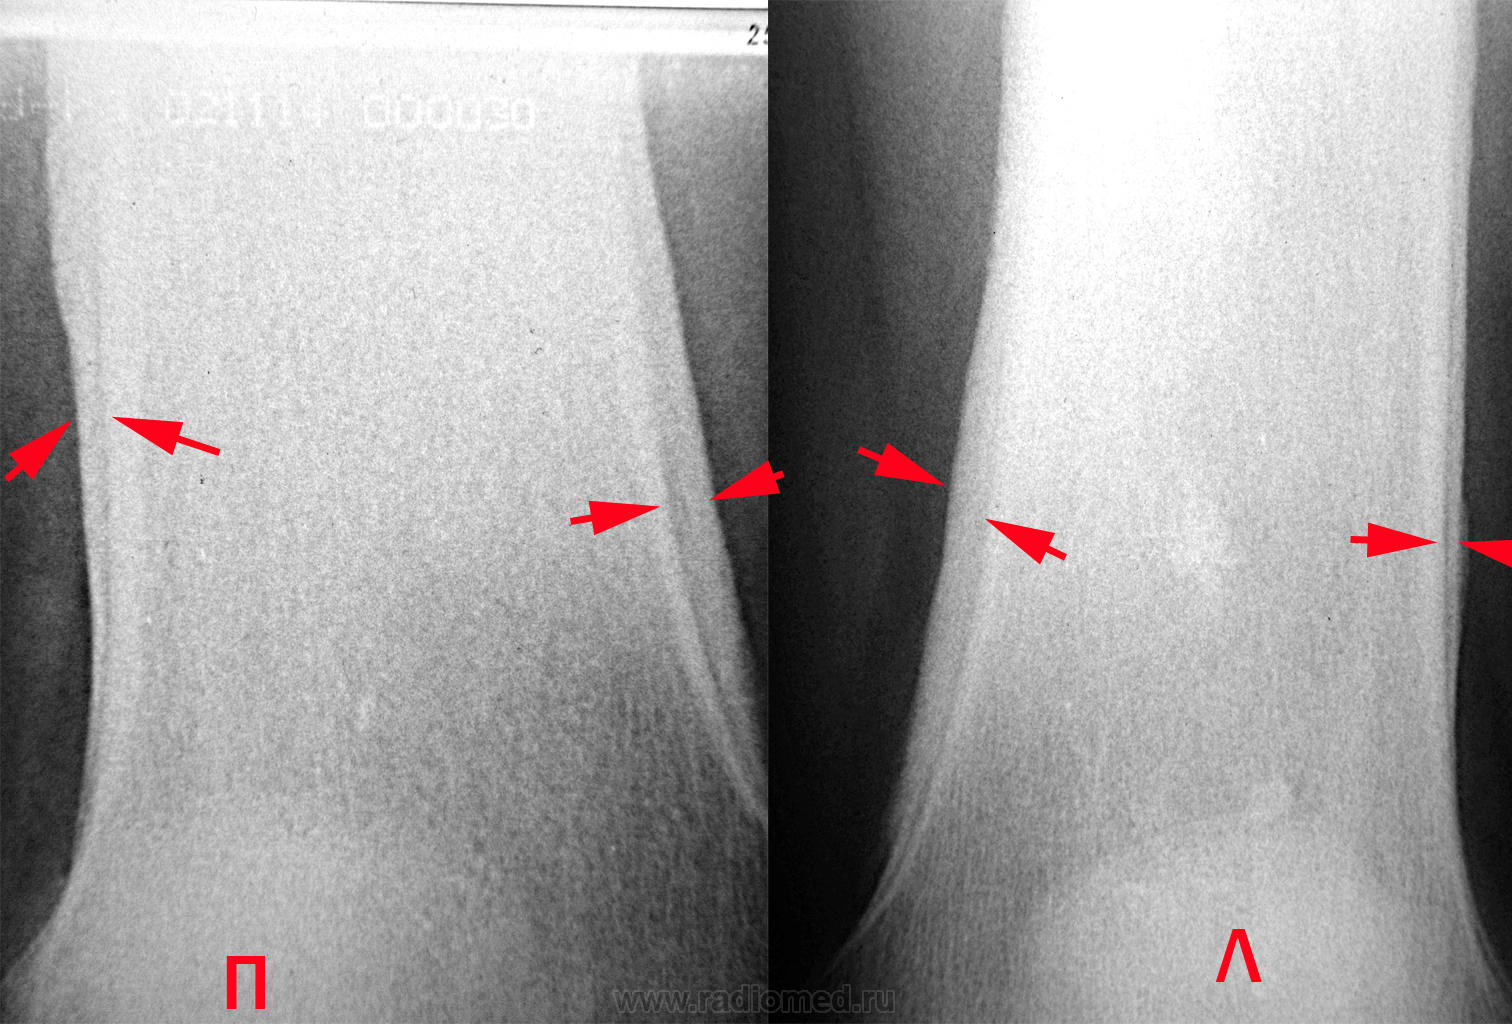

Рентгенологически Бамбергера - Мари периостоз проявляется утолщением диафизов симметричных костей за счет периостальных наслоений, которые выглядят ровными, гладкими, менее плотными, чем кортикальный слой диафизов. В дальнейшем периостальные наслоения могут приобретать плотность кортикального слоя и сливаться с ним. Типичны симметричность поражения и перестройка кортикального слоя в виде его продольной исчерченности.

Анатомическая и рентгенологическая картина системного оссифицирующего периостоза выражается в системном симметричном поражении преимущественно длинных трубчатых периферических костей (рис. 313). Больше всего изменены диафизы, отчасти также и метафизы костей предплечья и голени, пястных и плюсневых костей, а также основных и, средних фаланг. Эпифизы, лишенные надкостницы, остаются пощаженными. Важно, что оссифицирующую реакцию проявляет только надкостница, но не эндост, костномозговой канал трубчатой кости при этой болезни не суживается (рис. 314).

Надкостничные наслоения окутывают кости обыкновенно со всех сторон в виде футляра и имеют очень гладкую или местами несколько слегка шероховатую поверхность (рис. 316). Иногда видна продольная .слоистость надкостничных остеофитов. Нередко раньше и больше всего вовлекаются в процесс дистальные концы диафизов. У взрослого обычно окостеневает лишь самая наружная, поверхностная часть надкостничных наслоений, так что на рентгенограммах между корковым компактным веществом диафиза и узенькой плотной полоской оссифицированной надкостницы остается светлая продольная полоса (рис. 317). Новообразованная костная ткань вначале отличается по своей структуре от плотного основного вещества и на вскрытии даже сравнительно легко отделяется от поверхности диафиза. Но в дальнейшем, через месяцы у детей и через годы у взрослых, она сливается в единую костную массу. Толщина надкостничных разрастаний равна от 1 до 7 мм. Необходимо иметь в виду, что хронический пролиферативный процесс гистологически сопровождается резким утолщением обоих слоев надкостницы и чрезвычайным богатством сосудов; мы здесь наблюдали при диагностическом проколе кости и при биопсии очень сильные кровотечения. Структурный рисунок самой кости не представляет никаких уклонений от нормы. Эпифизар-ные линии остаются всегда неизмененными. Истинная генерализация, т. е. поражение всего скелета, включая обычно остающиеся пощаженными кости черепа, позвоночника, ключицы, губчатые кости запястья и лредшшсны, здесь крайне редкое явление.